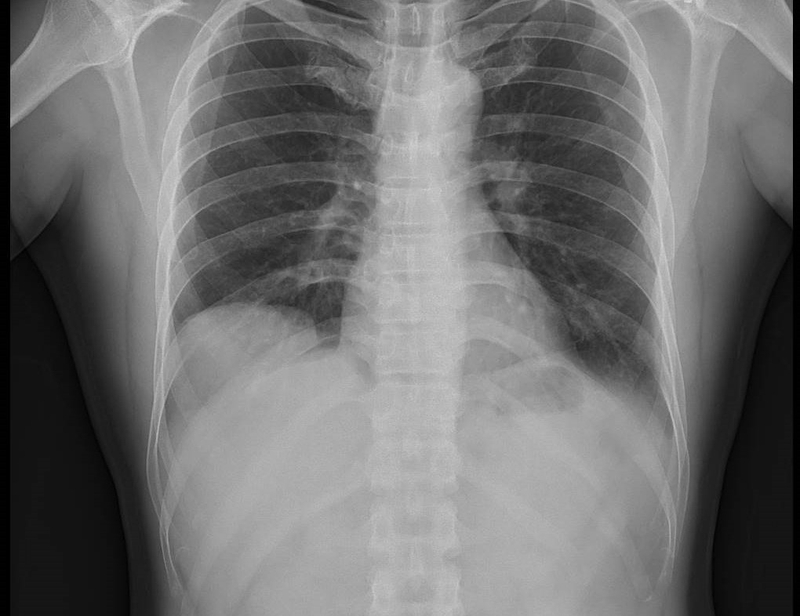

Chụp X-quang phổi thường được bác sĩ chỉ định trong quá trình kiểm tra và sàng lọc các bệnh lý liên quan đến phổi. Chụp X-quang phổi là phương pháp sử dụng tia X chiếu qua vùng lồng ngực đến một tấm phim nhựa hoặc một đầu thu đặc biệt có chức năng lưu lại hình ảnh của các cơ quan thuộc lồng ngực như tim, phổi, mạch máu, bộ xương thành ngực, đường thở,... Bên cạnh các xét nghiệm lâm sàng khác, một trong những chỉ định không thể thiếu nhằm đánh giá bệnh lý về phổi một cách toàn diện là chụp X-quang phổi. Đây là cách giúp chẩn đoán chính xác các bệnh về phổi.

Chụp X-quang phổi có vết mờ là hiện tượng thường thấy, thể hiện hình ảnh phổi bất thường, có vết mờ khác với phổi bình thường. Qua ảnh chụp thì chưa thể xác định được nguyên nhân dẫn đến vết mờ phổi, có thể là vết sẹo sau khi nhu mô phổi bị nhiễm trùng, chất kích thích có trong không khí hoặc bệnh ung thư phổi.

Chụp X-quang phổi có vết mờ khiến nhiều người lo lắng không biết bản thân có mắc bệnh lý nguy hiểm không. Nốt mờ phổi trên ảnh chụp thường có đường kính 1 - 10mm, có thể kết thành đám khoảng từ 1- 3 cm, khá nhỏ cho nên người bệnh có thể chưa xuất hiện triệu chứng lâm sàng của bệnh lý về phổi. Trên thực tế, chỉ dựa vào chụp X-quang phổi có vết mờ để khẳng định là bệnh ung thư hay không thì chưa đủ. Bệnh nhân sẽ được bác sĩ chỉ định thực hiện các phương pháp cần thiết khác như chụp CT scan ngực, chụp MRI, nội soi phế quản, PET hoặc sinh thiết mô phổi bất thường để có thể kết luận chính xác tình trạng của phổi sau khi chụp X-quang phổi có vết mờ. Việc chẩn đoán vết mờ phổi cần so sánh hình ảnh chụp X-quang chuẩn tư thế thẳng và ngang và cần so sánh với ảnh chụp trước đó.